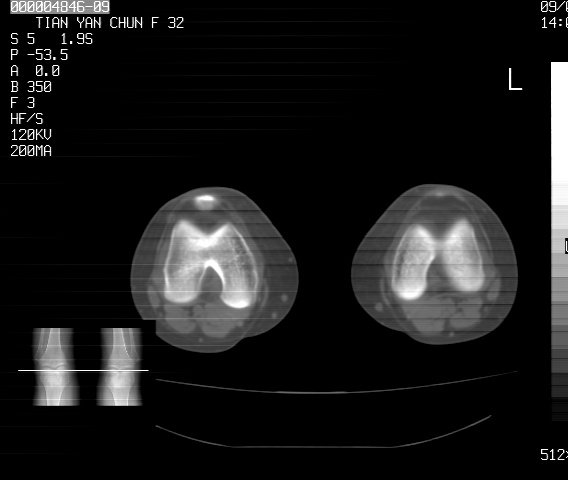

标题: CT18487:请会诊,女32岁,左膝疼痛数日 [打印本页]

标题: CT18487:请会诊,女32岁,左膝疼痛数日

关节面软骨有硬化环考虑退行性变

定位片可见髁间棘骨质增生,支持膝关节退行性变。

定位片可见髁间棘骨质增生,支持膝关节退行性变。建议mri 检查

考虑骨性关节炎